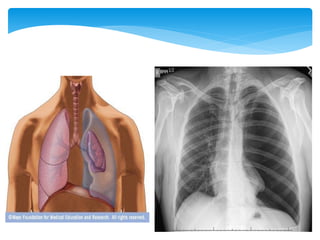

Composed of microscopic alveoli/alveolar sacs

(subdivision of the alveolar ducts)

Right lung has an upper, middle and lower lobe

Left lung has an upper and lower lobe

Covered by the visceral (internal) and parietal

(external) pleurae (pleural membranes)

Lungs

Composed of microscopicalveoli/alveolar sacs (subdivision of the alveolar ducts) Right lung has an upper, middle and lower lobe Left lung has an upper and lower lobe Covered by the visceral (internal) and parietal (external) pleurae (pleural membranes) Lungs